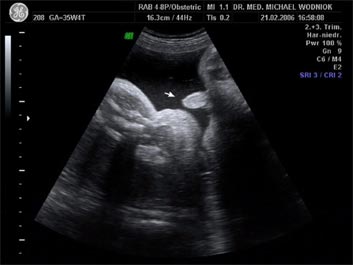

Im Rahmen der Mutterschaftsvorsorge wird mittels einer ersten Ultraschalluntersuchung frühzeitig die intakte Anlage des Embryos überprüft.

Im Verlauf der 5. SSW gelingt die Darstellung der Fruchthöhle mittels Vaginalultraschall bei normaler Anlage in der Gebärmutter. Die frühe Feststellung einer Fruchthöhle innerhalb der Gebärmutter schließt eine Eileiterschwangerschaft zu 99% aus. Am 34. Schwangerschaftstag (nach Regelblutung) ist diese 3mm groß. Die Darstellung der Herzaktion ist ab dem 48. Tag möglich. Ab einem mittleren Fruchthöhlendurchmesser von 20mm sollte die Herzaktion ebenfalls nachgewiesen werden können.

Weitere Ultraschalluntersuchungen sind in der 10./20./30. Schwangerschaftswoche gemäß den Mutterschaftsrichtlinien vorgesehen. Bei erkennbaren Risiken werden  weitere Untersuchungen angeschlossen. Spezielle Ultraschalluntersuchungen zum Ausschluss von kindlichen Entwicklungsstörungen sowie Durchblutungsmessungen der mütterlichen und kindlichen Blutgefäße mittels Farbdopplersonographie gehören zum Leistungsspektrum der Praxis. Auf Wunsch können auch 3D und 4D Untersuchungen angeboten werden.